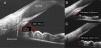

The iridocorneal angle, due to its implications in the physiopathology of aqueous humour drainage, is a fundamental structure of the anterior chamber. Anterior segment optical coherence tomography (AS−OCT) is a rapid and non-invasive technique that obtains images in vivo. The high resolution allows it to analyse the normal anatomy of the angle, any alterations, and the changes that occur after different therapeutic interventions. AS−OCT technology has evolved to provide images that allow the identification and quantification of the angular structures in healthy subjects and in glaucoma patients, and especially the trabecular meshwork and the Schlemm's canal. It also enables the angle width to be quantified, with some objective parameters that have been standardised in recent years, such as the trabecular-iris angle (TIA), the angle opening distance (AOD), and the trabecular-iris area (TISA). This technique has multiple uses in the study of the different mechanisms of angle closure, the evaluation of changes after a laser peripheral iridotomy or iridoplasty after cataract surgery, as well as after the implantation of phakic lenses.

El ángulo iridocorneal por sus implicaciones en la fisiopatología del drenaje del humor acuoso es una estructura fundamental de la cámara anterior. La tomografía de coherencia óptica de segmento anterior (OCT-SA) es una técnica rápida y no invasiva que obtiene imágenes de los tejidos vivos con una alta resolución permitiendo conocer la anatomía normal del ángulo, sus alteraciones y los cambios que se producen en el mismo tras diferentes intervenciones terapéuticas. La tecnología de la OCT-SA ha ido evolucionando hasta ofrecer imágenes que permiten identificar y cuantificar estructuras angulares claves en sujetos sanos y en pacientes con glaucoma, especialmente la malla trabecular y el canal de Schlemm, lo que puede contribuir a ampliar el conocimiento de la fisiopatología del glaucoma. Además, permite cuantificar la abertura angular con unos parámetros objetivos descritos en los últimos años, entre los que destacan el ángulo irido-trabecular (TIA), la distancia de abertura angular (AOD) y el área irido-trabecular (TISA). La OCT-SA presenta múltiples utilidades en el estudio de los distintos mecanismos del cierre angular, la evaluación de los cambios angulares tras la realización de una iridotomía láser o iridoplastia, cirugía de la catarata o el implante de lentes fáquicas.